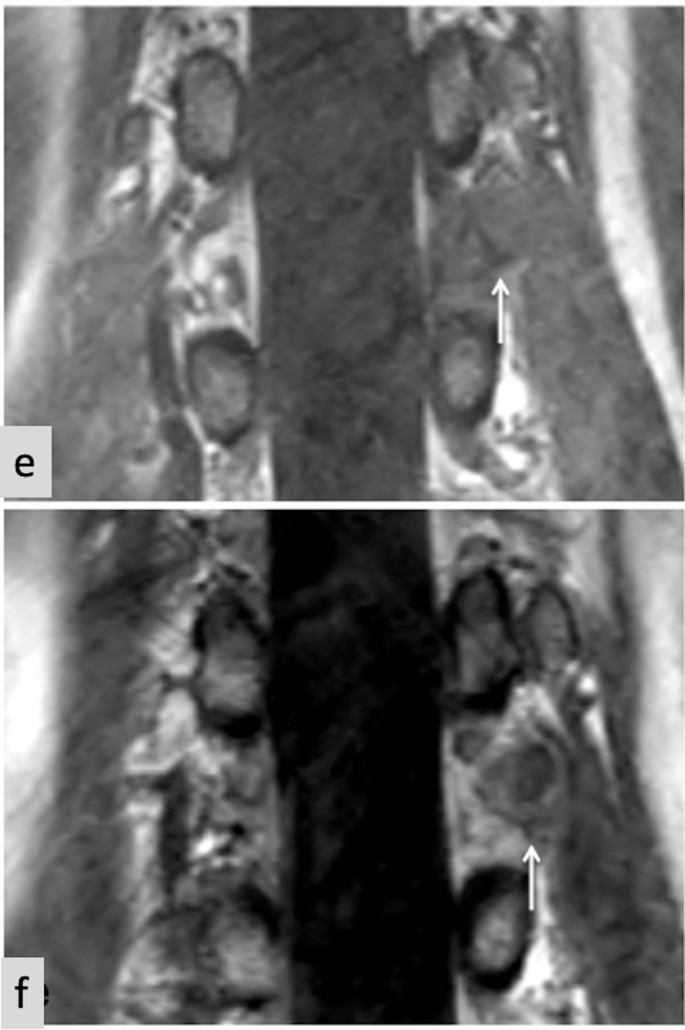

Fig. 3.

MRI thoracolumbar spine. a–d: Axial images at the T12/L1 level. e&f coronal images of thoracolumbar junction. All images show eccentric bulge of intervertebral disc contour that displaces left extraforaminal fat, and posteriorly displaces the left extraforaminal T12 nerve root. a) Axial T2. Disc bulge is hyperintense relative to skeletal muscle. b) Axial T1. Disc bulge is isointense relative to skeletal muscle. c) Axial STIR. Disc bulge is hyperintense relative to skeletal muscle. d) Axial T1FS post-contrast. Disc bulge demonstrates peripheral enhancement. e) Coronal T1. Disc bulge is isointense relative to skeletal muscle. f) Coronal T1FS post-contrast. Disc bulge demonstrates peripheral enhancement.